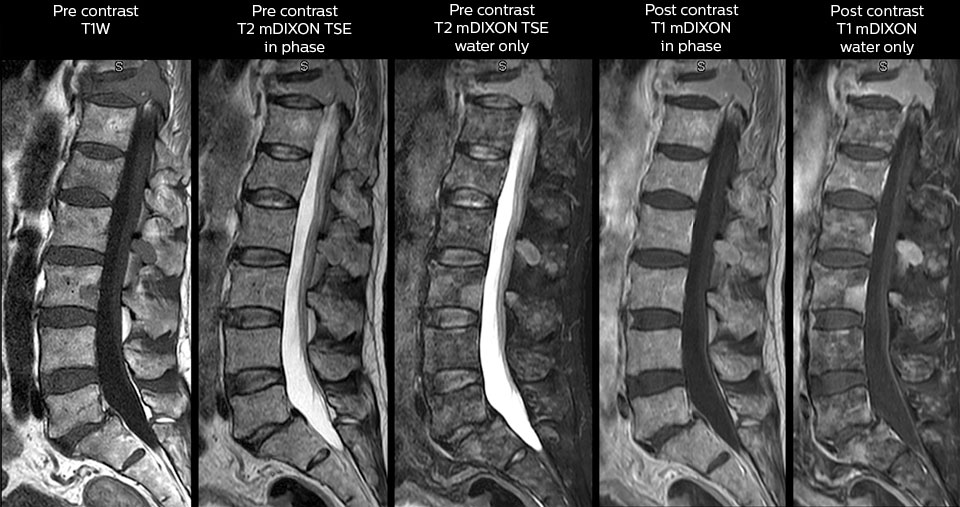

Including mDIXON TSE for robust fat suppression

“We use mDIXON TSE extensively in our spine imaging in the emergency room,” says Dr. Karis. “It’s particularly nice in that it is very robust with regard to susceptibility type of problems that would come up with traditional spectral fat-saturated images; these problems are essentially eliminated with the mDIXON technique. In our ED environment it’s really nice to have the fat-free imaging that goes along with the mDIXON technique.

“For the thoracic and cervical spine routine non-contrast exam, for example, we perform one mDIXON T2 TSE sequence, which provides us with two outputs: the fat-and-water-together T2-weighted images, as well as the water-only sagittal T2-weighted images. And then we also perform an axial gradient echo exam.”